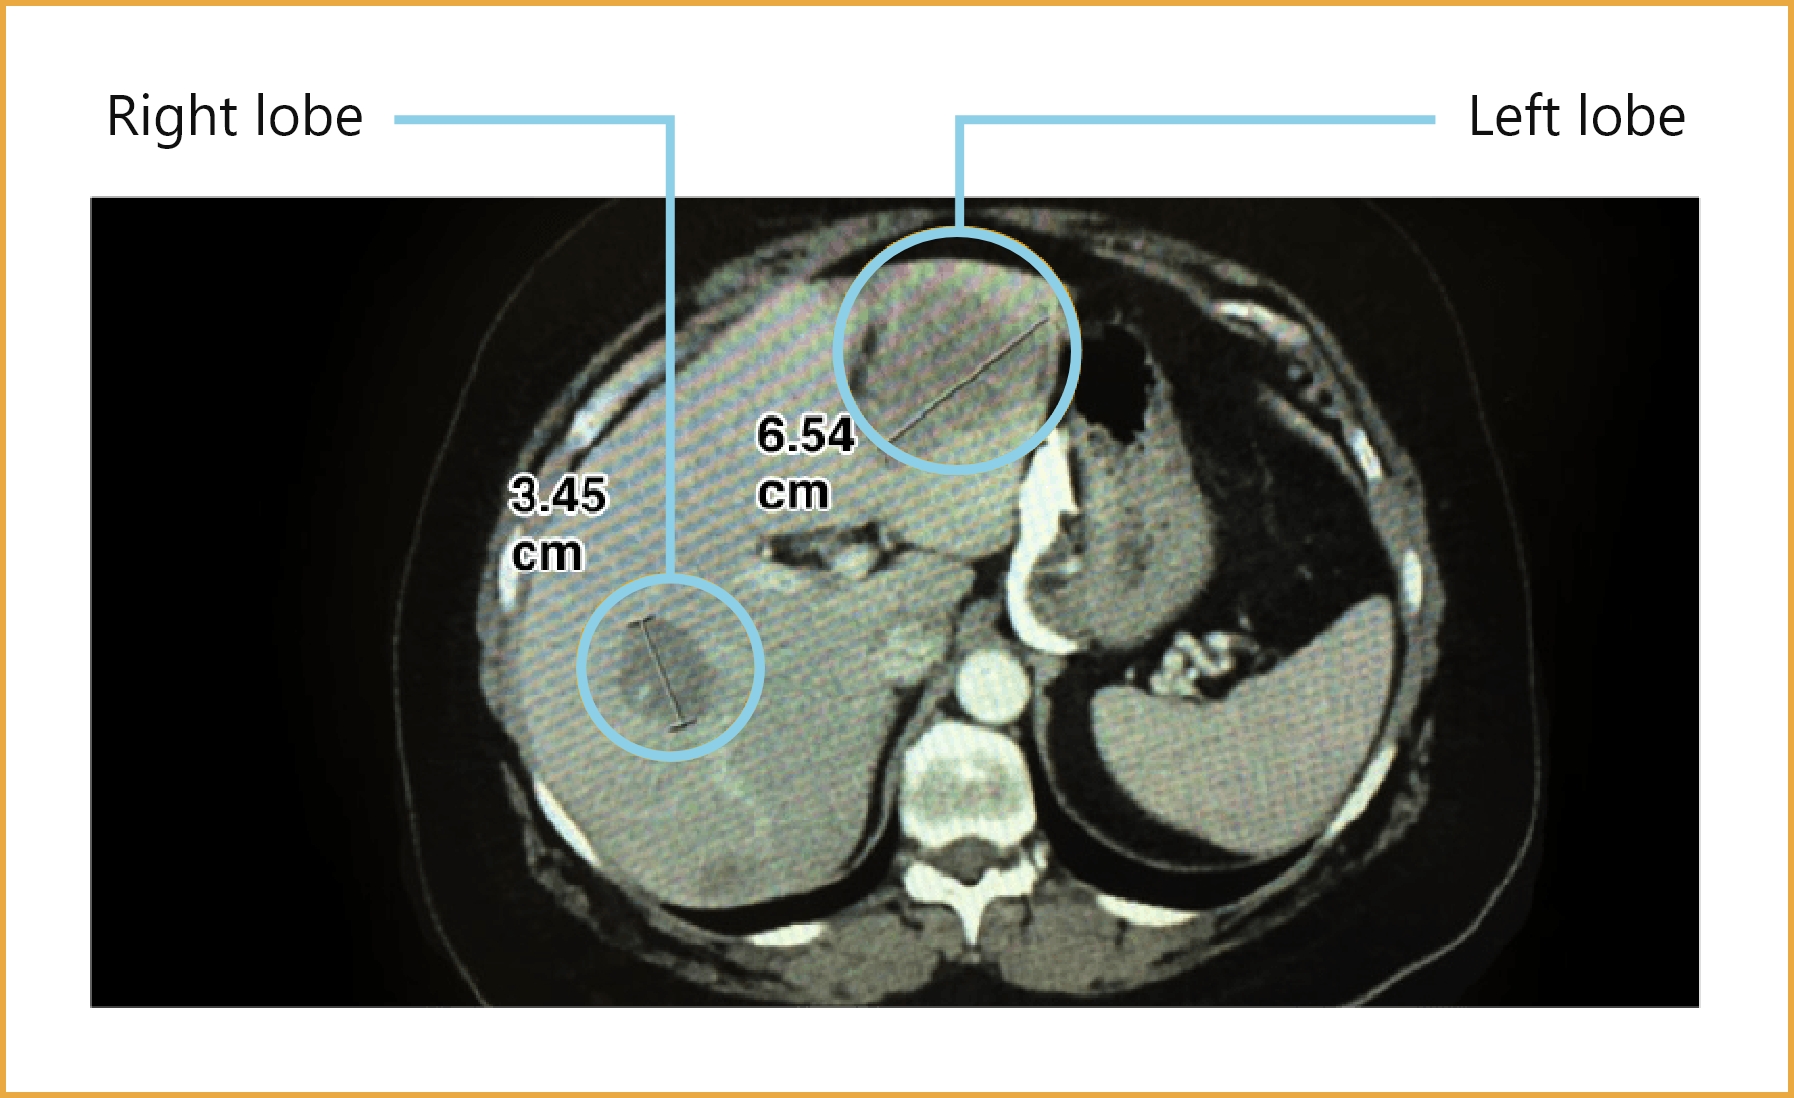

Imaging results

Images are shown for illustrative purposes only

*A hypothetical patient profile of treatment for a newly diagnosed mCRC patient.

ALT = alanine aminotransferase; AST = aspartate aminotransferase; CBC = complete blood count; CT = computed tomography; ECOG PS = Eastern Cooperative Oncology Group Performance Status; Hb = hemoglobin; mCRC = metastatic colorectal cancer; WT = wild type.

ALT = alanine aminotransferase; AST = aspartate aminotransferase; CBC = complete blood count; CT = computed tomography; ECOG PS = Eastern Cooperative Oncology Group Performance Status; GERD = gastroesophageal reflux disease; Hb = hemoglobin; mCRC = metastatic colorectal cancer; WT = wild type.